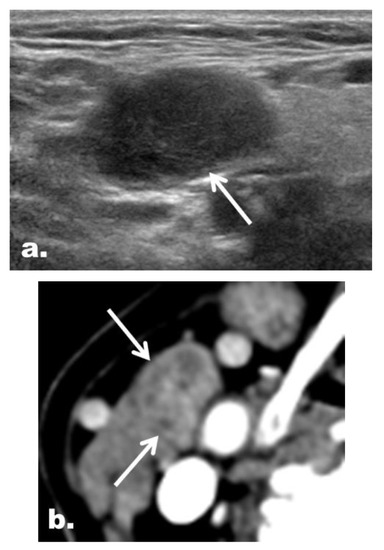

2.5. CT Imaging Features in the Reclassified Cases